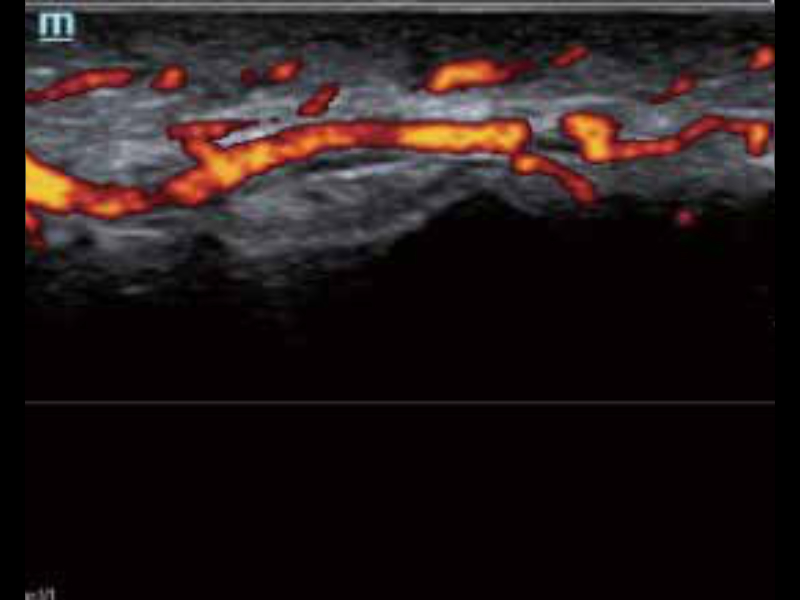

• zeus-fig5-2-3-uk

Doppler mocy – opuszka palca